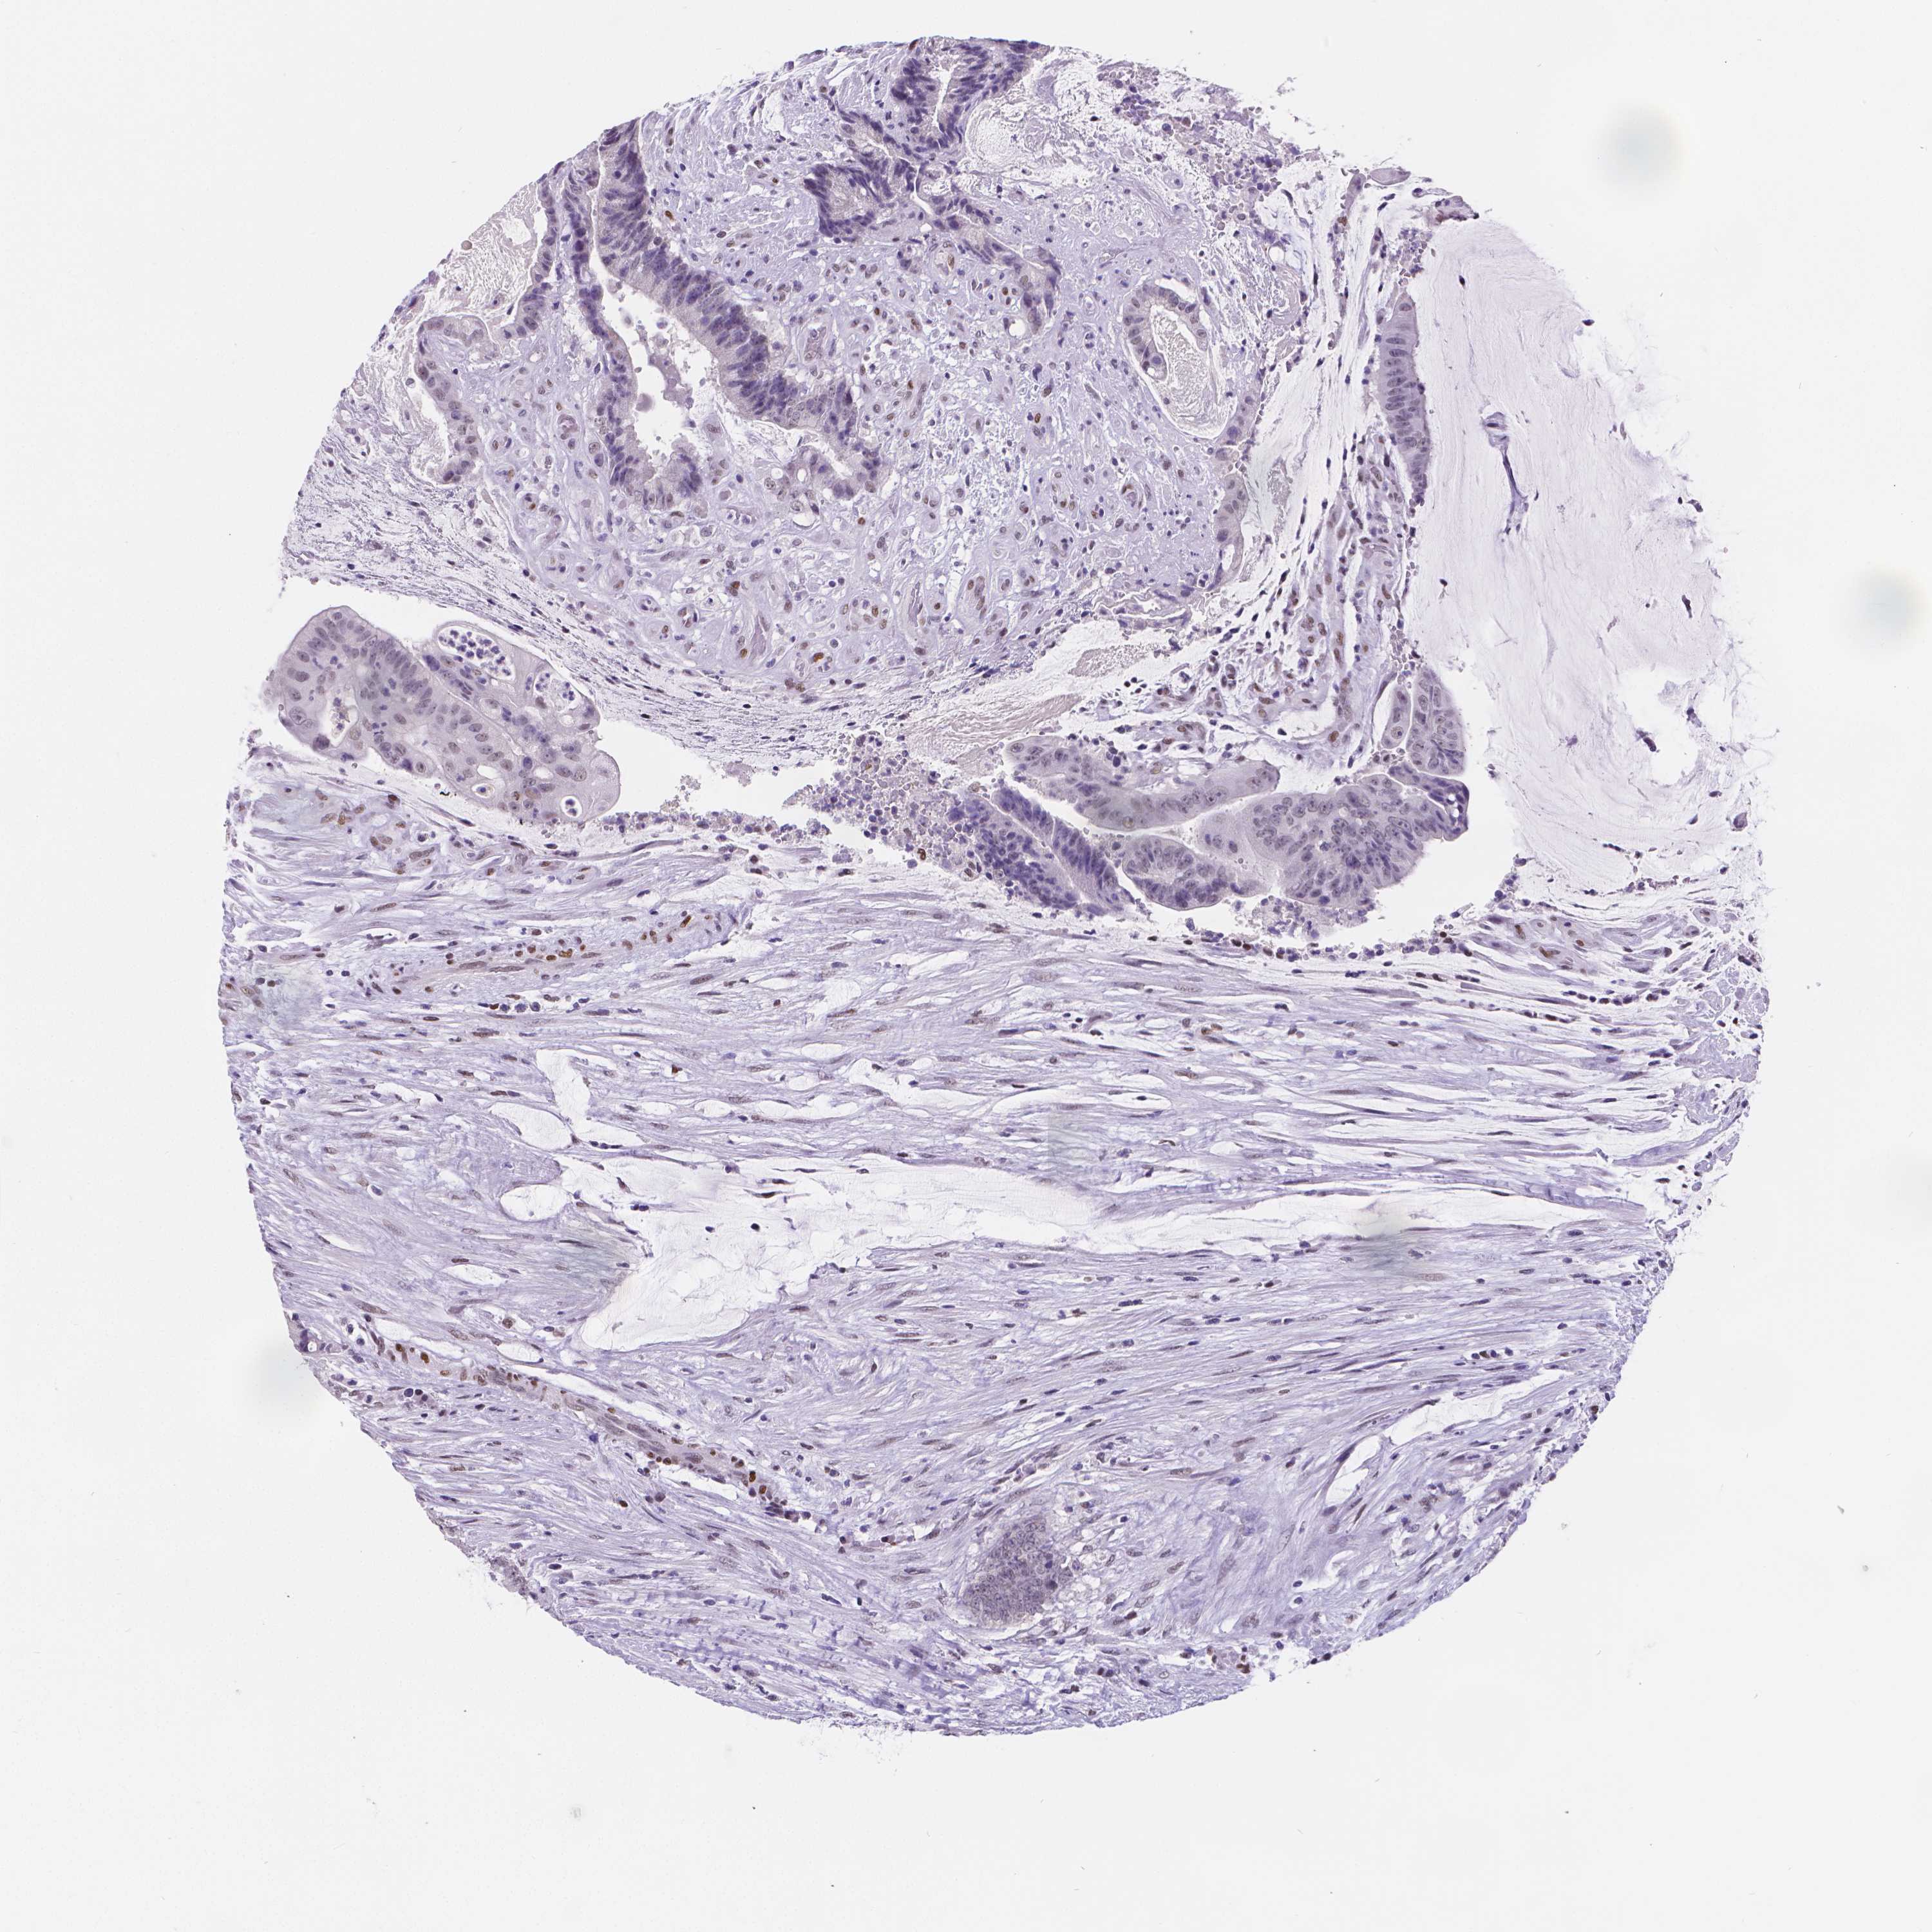

COAD TCGA COAD VALIDATION READ TCGA READ VALIDATION PROTEIN COAD CPTAC PROTEIN EXPRESSION

ANTIBODIES

AND

VALIDATION